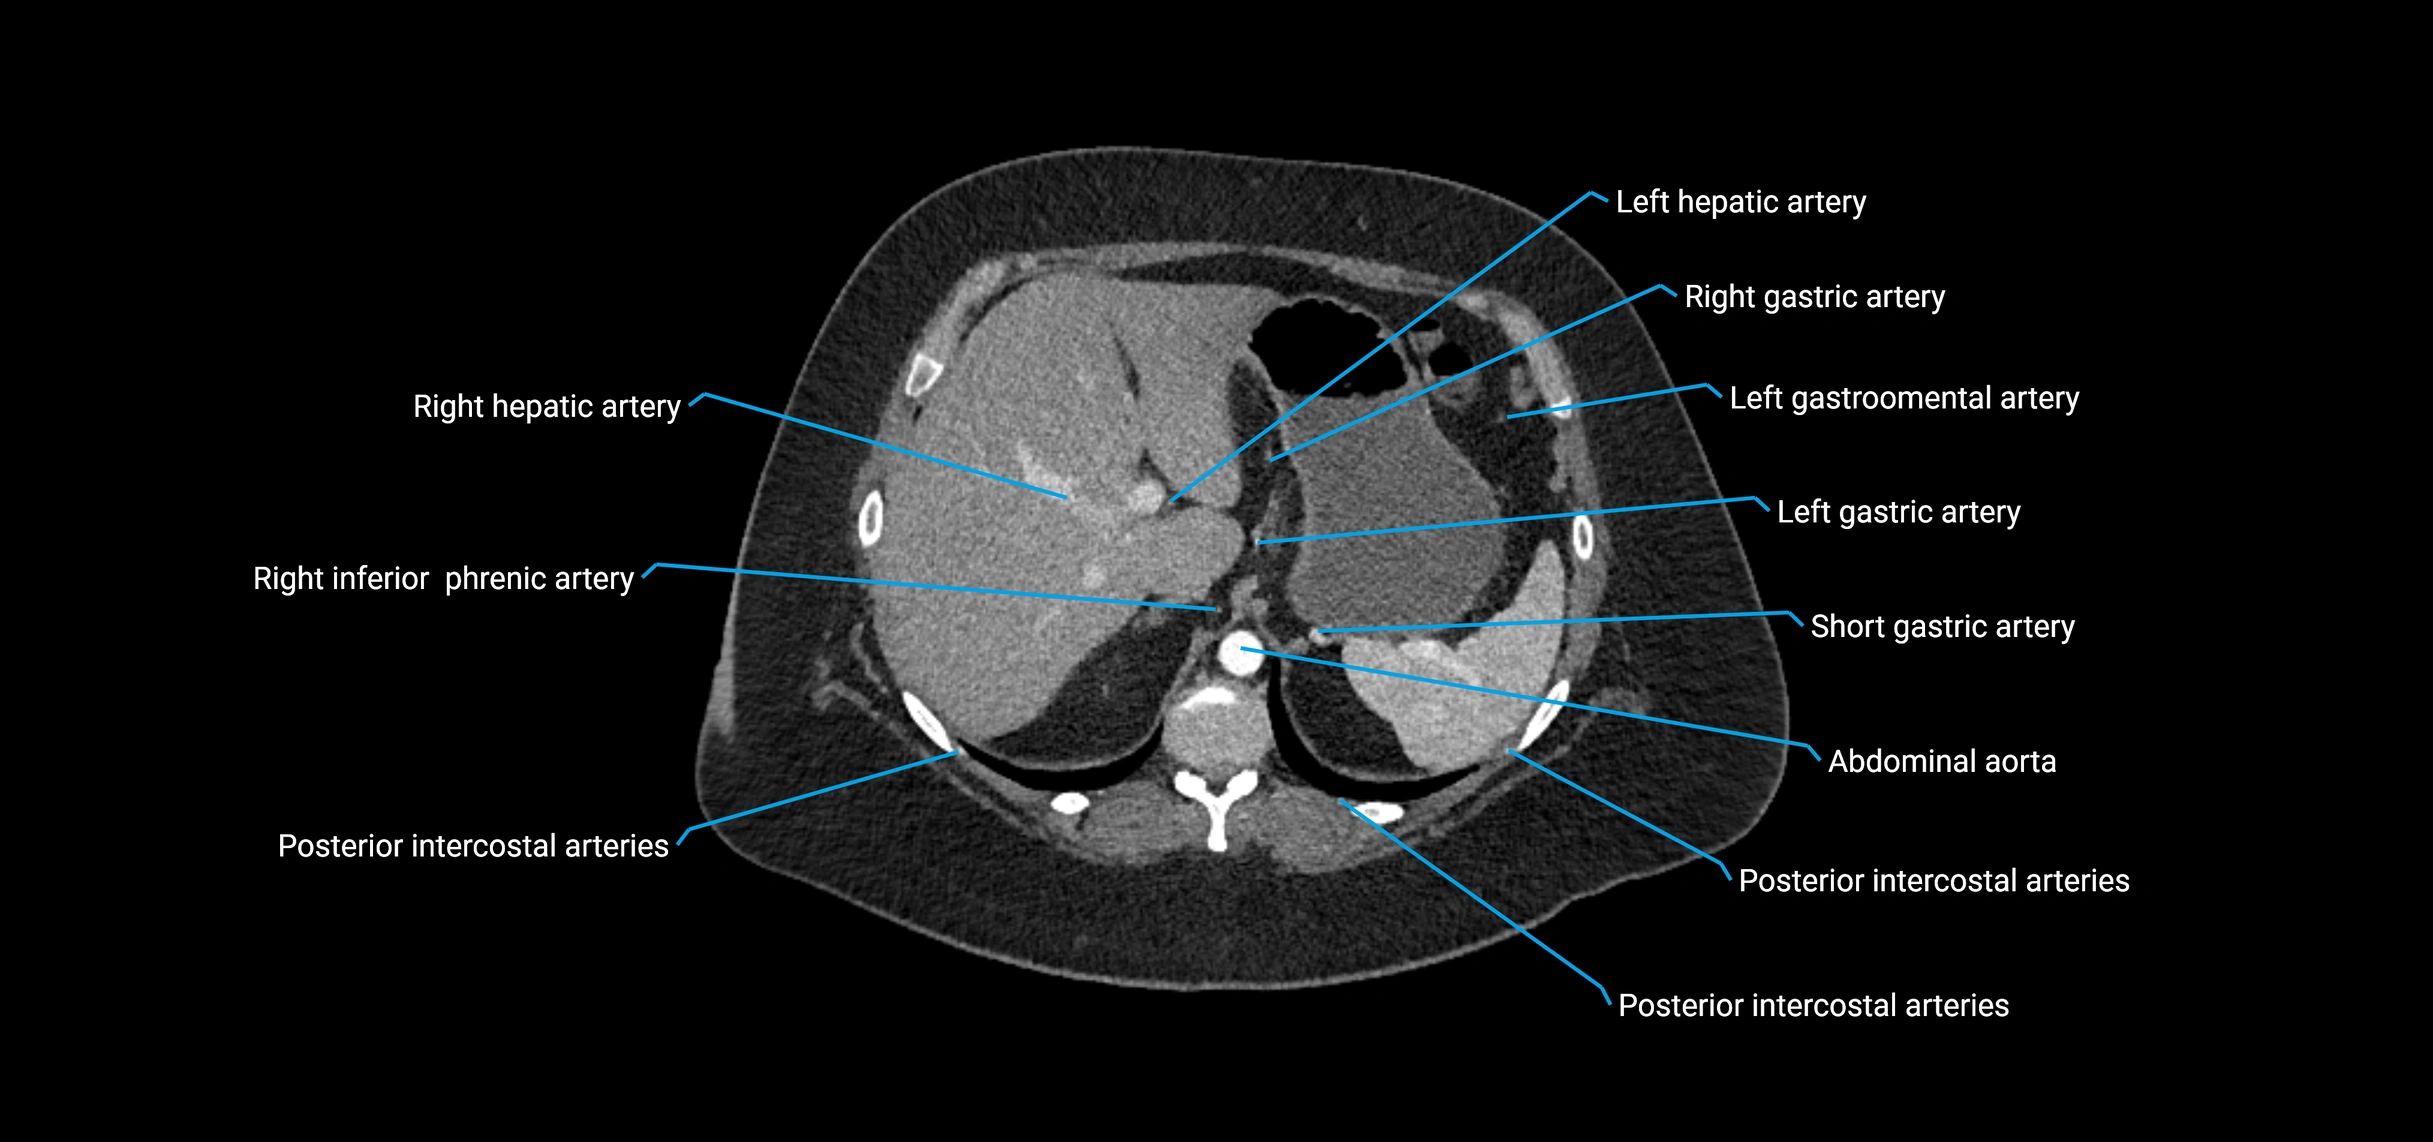

Contrast-enhanced CT (CTA):

• Gold standard for abdominal aortic imaging

• Provides excellent detail of lumen, wall, aneurysm, thrombus, and branch vessels

• Multiplanar and 3D reconstructions help in aneurysm measurement, stent graft planning, and dissection evaluation

• Detects acute rupture, traumatic injury, or occlusion with high sensitivity